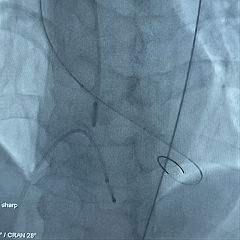

25号瓣膜释放至全展开

造影评估:瓣膜位置可,形态稳定

多角度评估,瓣膜位置可

脱钩后造影,瓣膜位置可,几乎无瓣周漏